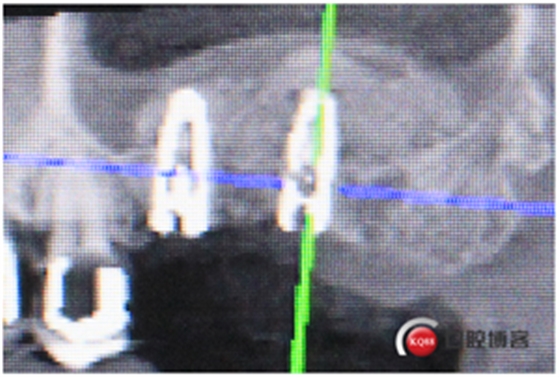

試戴冠,看起來還不錯哈,但我不滿意,大家看看有什么問題?看看下頜那幾顆比較明顯。

再看看片子。

問題在這里,不給留位置怎么會有齦乳頭,沒有間隙怎么清潔?這完全是技工的錯吧?算了我自己修整一下吧。

再看看是不是效果好多了?哼!我就是個較真兒的人。